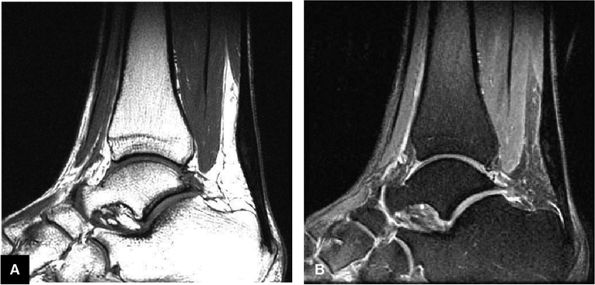

-

Achilles tendon rupture usually occurs 2 to 6 cm proximal to its os calcis insertion.

Sagittal images are used to identify the proximal and distal tendon ends.

Axial FS PD FSE images are used to confirm complete rupture (an intact plantaris may simulate an intact tendon in the sagittal plane).

A fluid-filled gap with or without interposed fat at the tear site in complete tendinous disruptions with discontinuity

Fraying or corkscrewing (see Fig. 5.123) of the tendon edges associated with proximal tendon retraction

In the absence of overlapping tendon edges, no tendon fibers can be seen at the tear site on axial images.

Tendon disruption with discontinuity and a wavy retracted tendon

Associated hemorrhage or edema in intratendinous or peritendinous soft tissues on axial or sagittal images

Disruption of muscle fibers in a musculotendinous junction tear, although on gross examination the tendon appears intact

Effacement of Kager's triangle18

Intratendinous degeneration

Partial tears demonstrate hyperintense signal with incomplete anterior-to-posterior or posterior-to-anterior extension on FS PD FSE images.

Complete tears demonstrate a hyperintense fluid-filled tendinous gap.

Tendon rupture usually occurs 2 to 6 cm superior to the os calcis.

The size of the rupture varies, based on the degree of tendon retraction.

Ruptures demonstrate diffuse convexity of the anterior margin and enlarged tendon ends at the tear site.